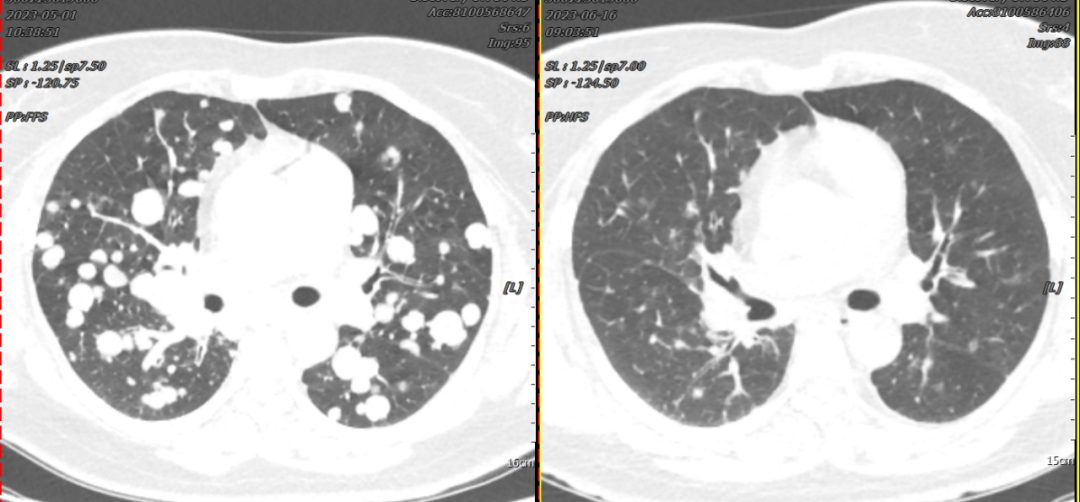

Patient Song XX, female, 41 years old, presented with cough, expectoration, accompanied by chest tightness and shortness of breath. In May 2023, a chest CT scan performed at our hospital revealed a mass near the hilum of the right upper lobe with diffuse multiple nodules distributed in both lungs, stenosis and occlusion of the right upper lobe bronchus, and encasement of the right upper pulmonary artery and brachiocephalic veins, suggesting right lung cancer with bilateral lung metastases. Subsequently, a CT-guided lung biopsy was performed, and pathological examination confirmed right lung invasive adenocarcinoma. Genetic testing showed an EGFR-19Del mutation. The diagnosis was "right lung adenocarcinoma, driver gene-positive (EGFR-19Del mutation)." After oral targeted therapy, the patient's cough, chest tightness, and shortness of breath significantly improved. A follow-up chest CT one month later showed significant shrinkage of the lung lesions, with most tumors gradually disappearing. The clinical efficacy was evaluated as PR (Partial Response).